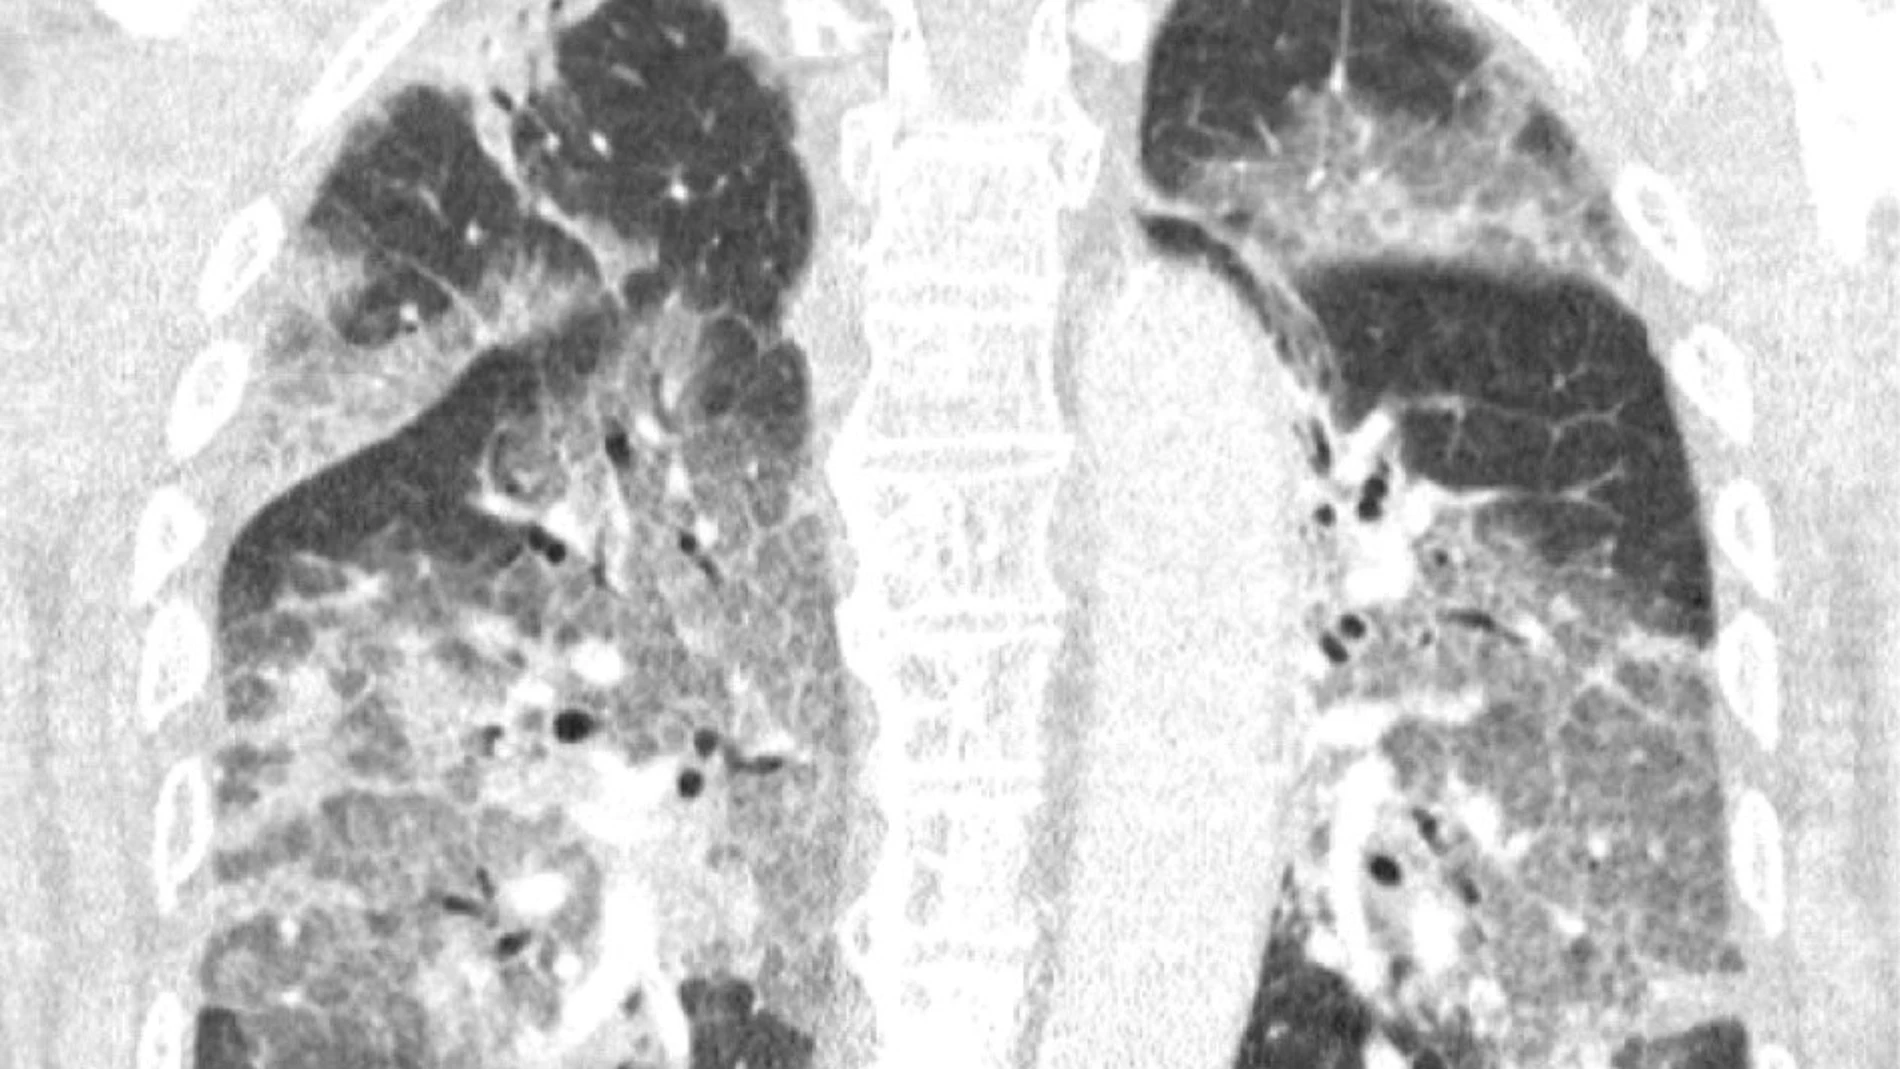

La carta abierta de estos sanitarios neerlandeses, acompañada de una radiografía de los pulmones de su paciente que no deja indiferente, va dirigida al ministro de Sanidad en funciones, Hugo de Jonge, en una crítica a la paralización del uso de Janssen, filial de Johnson & Johnson, y de las limitaciones de edad impuestas al uso de AstraZeneca.

“Hoy ingresó en nuestro hospital el primer paciente que se había negado a recibir la vacuna de AstraZeneca tras toda la conmoción en la prensa. Oímos el tremendo pesar en su voz y la desesperación en sus ojos. El virus lo ha atacado y podría haberse evitado. Con su permiso, compartimos su escáner de pulmón. No es necesario ser un especialista en pulmones para reconocer la devastación, ni epidemiólogo para explicar los riesgos de no estar vacunado”, alertaron.